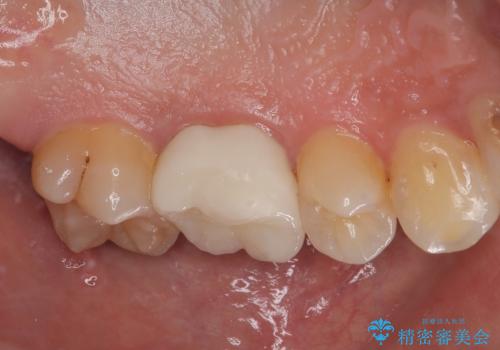

違和感が全くないと喜んでいただきました。

矯正治療後の後戻りのチェックを行いながらメインテナンスで通ってもらいながら経過を見る予定です。